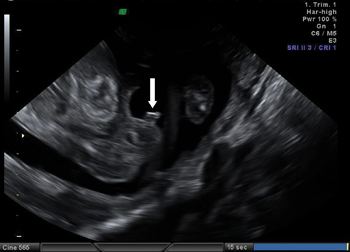

يعتمد التشخيص الجنسي للجنين على العلامة السهمية وهي اتجاه الحديبة التناسلية - يشير الاتجاه الصاعد إلى جنين ذكر، والاتجاه الهابط يشير إلى جنين أنثى

هنا يظهر جنين ذكر